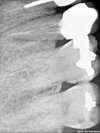

Voici le cas d'une dent infectée et cassée qui doit être extraite.

2 ème prémolaire maxillaire droite.

Mais entre la découverte et l'extraction, le temps était passé et la perte osseuse s'est révélée importante : plus d'os de l'extérieur à l'intérieur.

Le forage se fait au delà.

L'implant est posé et stabilisé (car il en est capable : importance de la marque et des caractéristiques techniques)

Un comblement osseux (triphosphate calcique et non

d'origine animale ou humaine : loi de Juillet 2009) est posé autour pour reconstituer les manques.

Une membrane referme le site et la gencive est refermée par dessus.